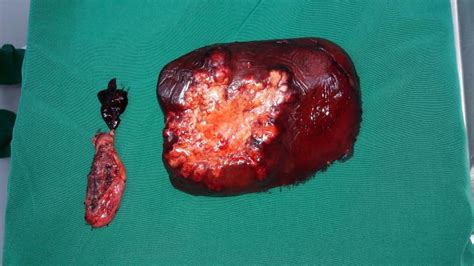

Tumores En El Higado En Perros, , , , , , , 0, Veterinary Key Points: Message to Massive Liver Tumors in Dogs: We are, drstephenbirchard.blogspot.com, 1000 x 750, jpeg, WebComo ya hemos comentado, en los perros son más frecuentes los tumores hepáticos malignos. Además, es más frecuente el cáncer de hígado en perros mayores. En concreto, el carcinoma hepatocelular es el cáncer de hígado canino más frecuente,. WebLos carcinomas de vías biliares son los tumores de hígado malignos más frecuentes en gatos y el segundo tipo de tumor de hígado más frecuente en perros. Los tumores de. WebEl tumor de bazo es un tipo de cáncer que es común en perros y relativamente raro y sus signos a menudo dependen de la localización del tumor, que., 20, tumores-en-el-higado-en-perros, Novedades y Muebles WebComo ya hemos comentado, en los perros son más frecuentes los tumores hepáticos malignos. Además, es más frecuente el cáncer de hígado en perros mayores. En concreto, el carcinoma hepatocelular es el cáncer de hígado canino más frecuente,. WebLos carcinomas de vías biliares son los tumores de hígado malignos más frecuentes en gatos y el segundo tipo de tumor de hígado más frecuente en perros. Los tumores de. WebEl tumor de bazo es un tipo de cáncer que es común en perros y relativamente raro y sus signos a menudo dependen de la localización del tumor, que.

WebTipos de cáncer de hígado en perros. Estos son los tipos de carcinomas hepatocelulares (cáncer de hígado en perros síntomas): Masivo: un tumor grande y único que. WebLa presencia de un tumor en un perro del hígado no siempre significa que el cáncer. Hay varios tipos de tumores benignos en el hígado que puede ocurrir en perros..

Veterinary Key Points: Message to Massive Liver Tumors in Dogs: We are

Source: drstephenbirchard.blogspot.com

WebComo todos los tumores, el tumor de hígado en perros se origina debido a una mutación en el ADN de una o varias células hepáticas. Como consecuencia, estas. WebCáncer de hígado en los perros suelen ser causados por un tumor maligno llamado carcinoma hepatocelular. Este tumor maligno se forma en el tejido. WebMás del 50% de los cánceres de hígado en perros son carcinomas hepatocelulares. Estos comienzan en el hígado y rara vez se diseminan fuera del hígado, pero suelen ser. WebEl cáncer de hígado en los perros suele estar causado por un tumor maligno llamado carcinoma hepatocelular. Este tumor maligno se forma en el tejido que recubre las. WebSi su perro ha sido diagnosticado con un tumor canceroso en el hígado, puede significar una de estas dos cosas. O bien su perro tiene cáncer de hígado, o su. WebEn concreto, el carcinoma hepatocelular es el tumor hepático más frecuente en los perros, seguido del carcinoma de vías biliares. Síntomas de los. WebLa hiperplasia nodular hepática es una lesión aparentemente benigna que se encuentra en el hígado de los perros de mediana edad a viejos. La lesión consiste en acumulaciones.